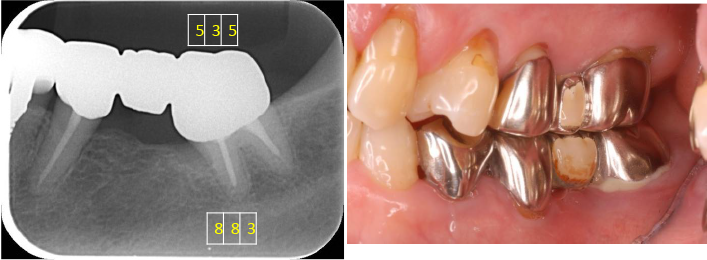

口腔内写真5枚法

主訴のむし歯というのは右上3番でした。

右上2番は先天欠損です。

初診時デンタル及びプロービングチャート

右上6番7番右下7、左下7番および左上7番には深いポケットがみられます。

左下7の近心には垂直性の骨欠損を認めます。

X線上では分かりにくいですが右下7には歯根に及ぶカリエスを認め、

また右下5には破折したリーマーと根尖病変を認めました。

右下5番は残念ながら再治療が不可能と判断し抜歯、右下7番もむし歯が進行しすぎているため保存ができないと判断し抜歯としました。

患者さんはなくなってしまった部位にたいして、インプラント治療を希望されたためインプラントにて治療をすることにしました。

CT所見

ほぼ骨内には埋入できましたが、骨の厚みが足りないため、人工骨を移植し縫合しました。

埋入後6カ月口腔内写真及びデンタル

インプラントの周囲に固い歯茎(角化歯肉)があるとしっかりと歯ブラシがあてることができます。

インプラントの周囲に固い歯茎を作るために歯茎(角化歯肉)の移植を行いました。